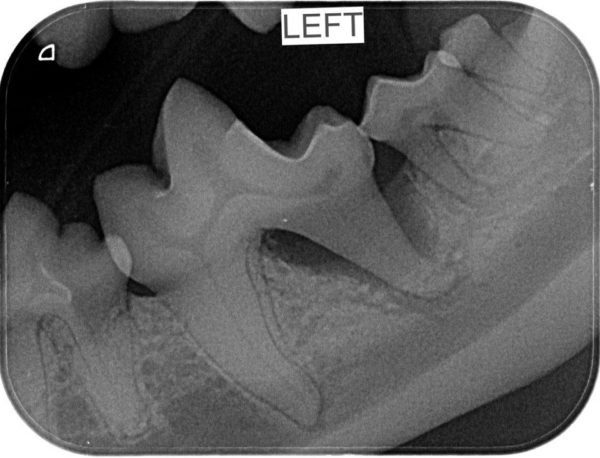

Then your pet is not alone. 80% of pets that we see do need some dental attention. The good news is that a Scale, Polish & Assessment (or SPA) is a routine procedure and we do them every day, so our vets and nurses are really experienced. Part of your pets SPA Procedure will involve dental X-rays which are essential for us to fully assess what is happening in your pet’s mouth. The dental X-rays above belong to Gus, who is a Miniature Schnauzer. Gus came in for a Healthy Pets 4 Life check-up and dental and although his mouth appears normal to the eye, the X-rays revealed disease below the gum line that needed our attention; luckily we caught it on the X-rays. It was after treating Gus that we began to include dental X-rays in our routine dental procedures so we didn’t miss any more sore teeth that needed treating.

This picture shows a healthy gum line – you can see the healthy tooth roots below the gum line which in the grey area